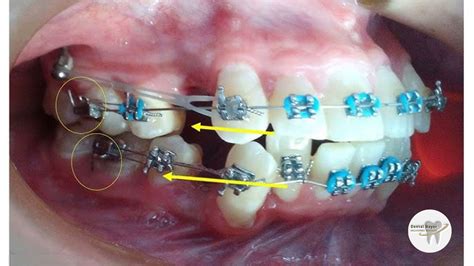

Los elásticos intraorales se pueden colocar sobre los brackets en caso de ortodoncia convencional o sobre los botones en caso de alineadores.

- Para cerrar el espacio entre los dientes: se colocan desde el primer o segundo molar superior hasta el gancho de la cúspide superior.

- En maloclusiones de clase 2: para reforzar el anclaje en caso de haber realizado una extracción, para permitir que los incisivos maxilares se muevan hacia atrás o para corregir la desviación de la línea media y permitir el movimiento bucal de los incisivos inferiores con punta hacia atrás: en estos casos se utilizan desde el primer molar inferior hasta el diente canino superior.

- En relaciones molares que se acercan a la maloclusión de clase 1: sobre todo para corregir un prognatismo retrayendo los dientes inferiores y adelantando los superiores.